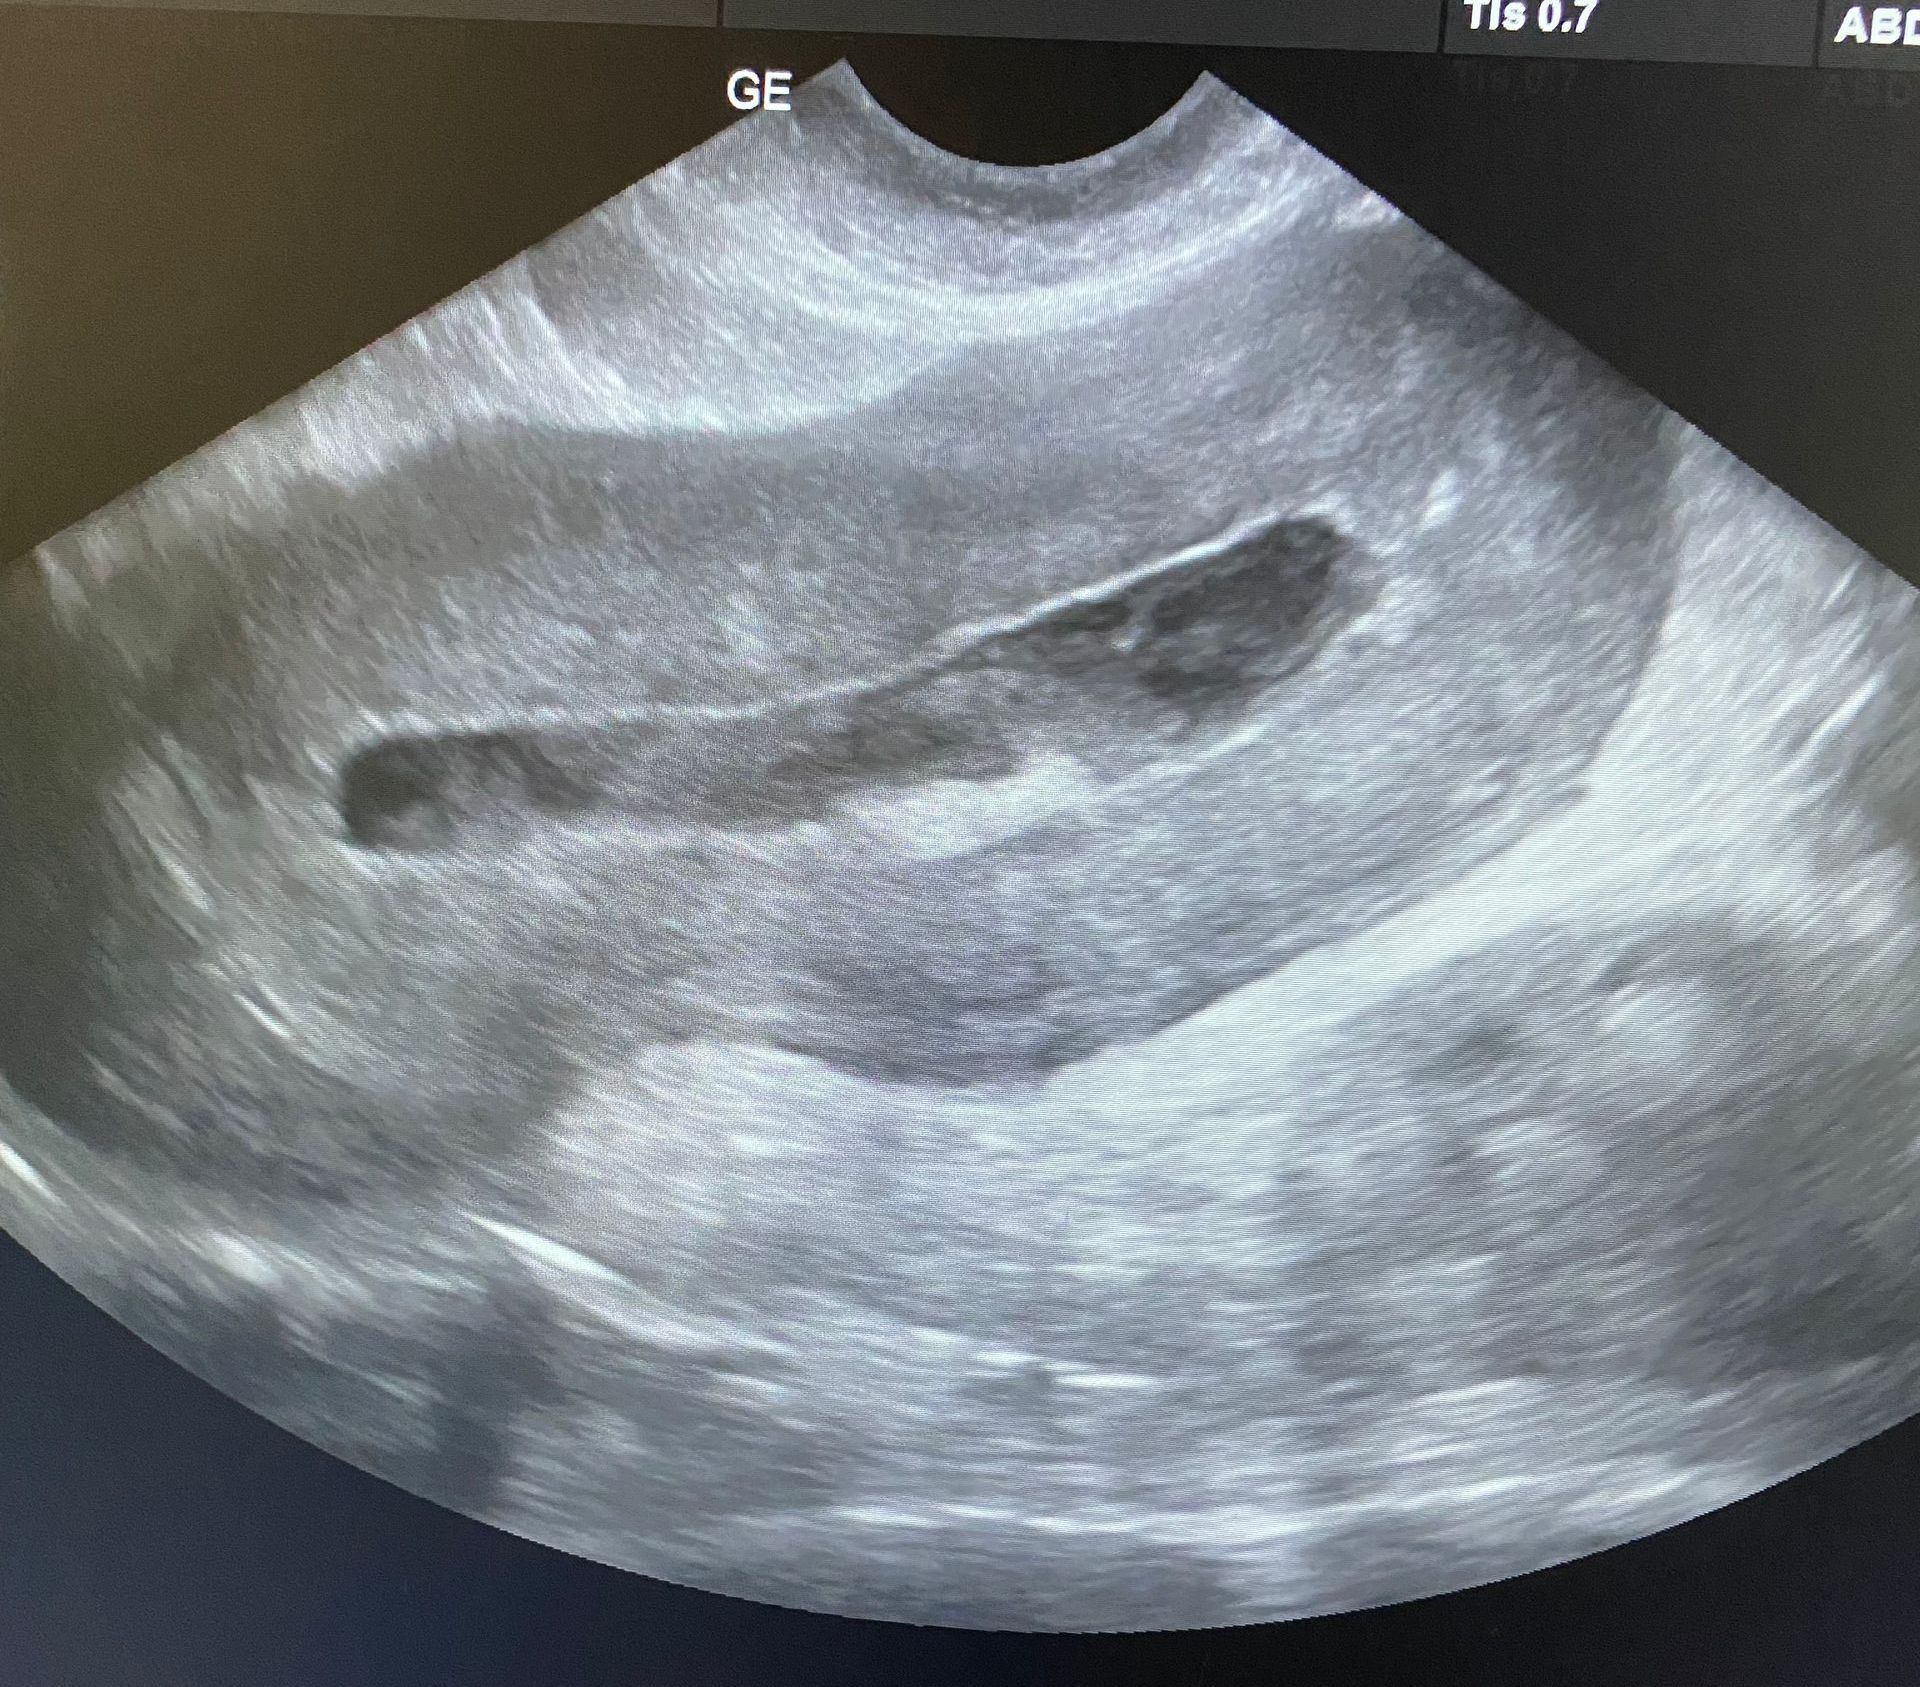

- Echographie Abdominale

L'Échographie est préconisée lors de douleurs abdominales, de dysfonctionnements organiques, de suspicion de masse abdominale ou d’épanchement, de troubles urinaires ou génitaux ou d'un bilan sanguin avec des anomalies.